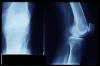

Prótesis completa de rodilla. Situación postquirúrgica.

Prótesis completa de rodilla. Situación postquirúrgica. Lateral.

Prótesis completa de rodilla.Lateral.

Prótesis completa de rodilla. Frontal.

Prótesis completa bilateral de rodillas.